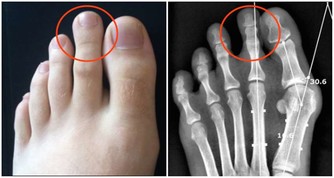

不少人常年都被痔瘡所困擾,雖然這類疾病通常不會威脅到患者生命,但會在一定程度上妨礙到正常生活。痔瘡主要分為兩種類型,內痔和外痔。外痔生長於肛門周圍的皮膚組織,可以直接用肉眼觀察到;痔核位於肛門內側粘膜時,通常屬於內痔。